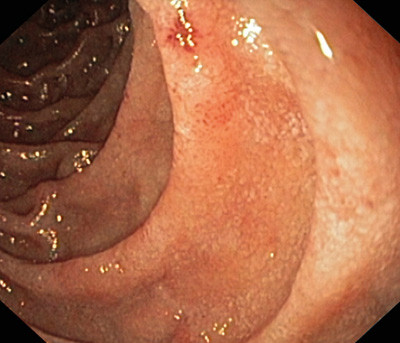

Ved oppfølgende enteroskopi fant man fortsatt noe ventrikkelretensjon. Slimhinnene i antrum, duodenum og øvre del av jejunum var lett betente (fig 2), men forandringene var relativt beskjedne sett i lys av sykdomsbildet. Histologiske prøver av endoskopiske biopsier fra tynntarm (fig 3) viste infiltrasjon av eosinofile granulocytter med opp mot 50 celler per synsfelt, vesentlig i lamina propria, forenlig med eosinofil gastroenteritt.

De endoskopiske funnene er uspesifikke. Man kan finne erytem, ødem og fortykkede slimhinnefolder (12, 15). Forandringene er ofte sparsomme og korrelerer ikke nødvendigvis med de kliniske symptomene, og kan dermed være vanskelige å legge merke til. Det er heller ikke uvanlig at slimhinnene er makroskopisk normale. Hos noen kan imidlertid forandringene være mer uttalte, med lettblødende slimhinner og ulcerasjoner (15, 18).